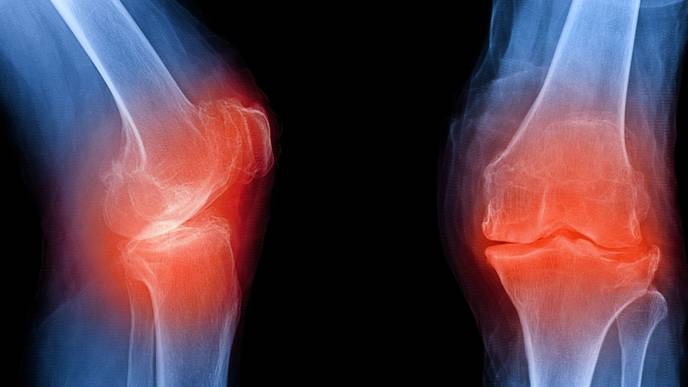

Osteoarthritis is the most common form of arthritis, and it affects more than 32.5 million adults in the U.S. It was originally known as a "wear and tear" disease because it occurs when cartilage within a joint — usually in the hands, hips and knees — breaks down. This causes the underlying bone to change over time, leading to pain, stiffness and swelling.

However, evidence now suggests that inflammation is an integral driver of the joint damage seen in osteoarthritis. This means that there could be "biomarkers," or measurable signs in the body, that could signal that the disease is kicking off long before structural damage is picked up by an X-ray.